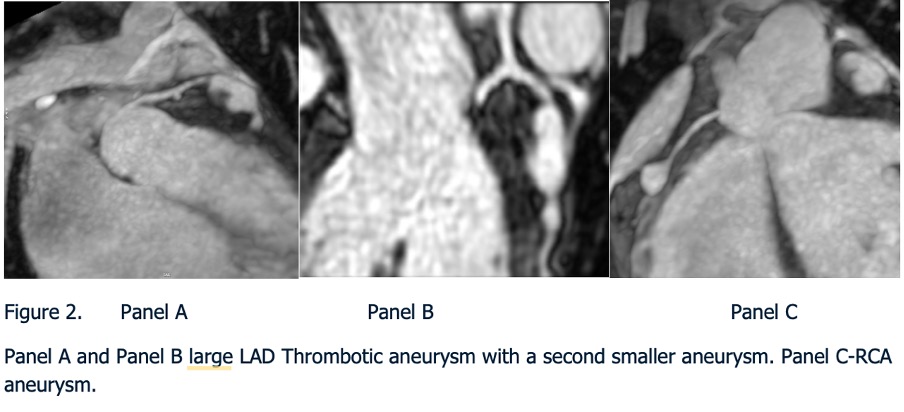

Panel A and Panel B large LAD Thrombotic aneurysm with a second smaller aneurysm. Panel C-RCA aneurysm.